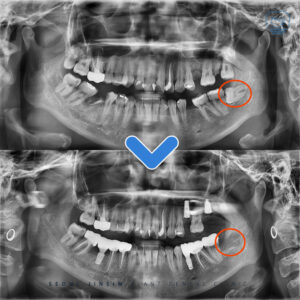

수원정자동치과 고난이도 상악동거상술 임플란트 잘하는 치과 . 안녕하세요 수원정자동치과 서울진심플란트치과입니다. 오늘은 저희 치과에서 진행한 고난이도 상악동 거상술을 포함한 임플란트 치료 사례를 소개해 드리겠습니다. . . 위 환자분께서는 몇 달 전,…